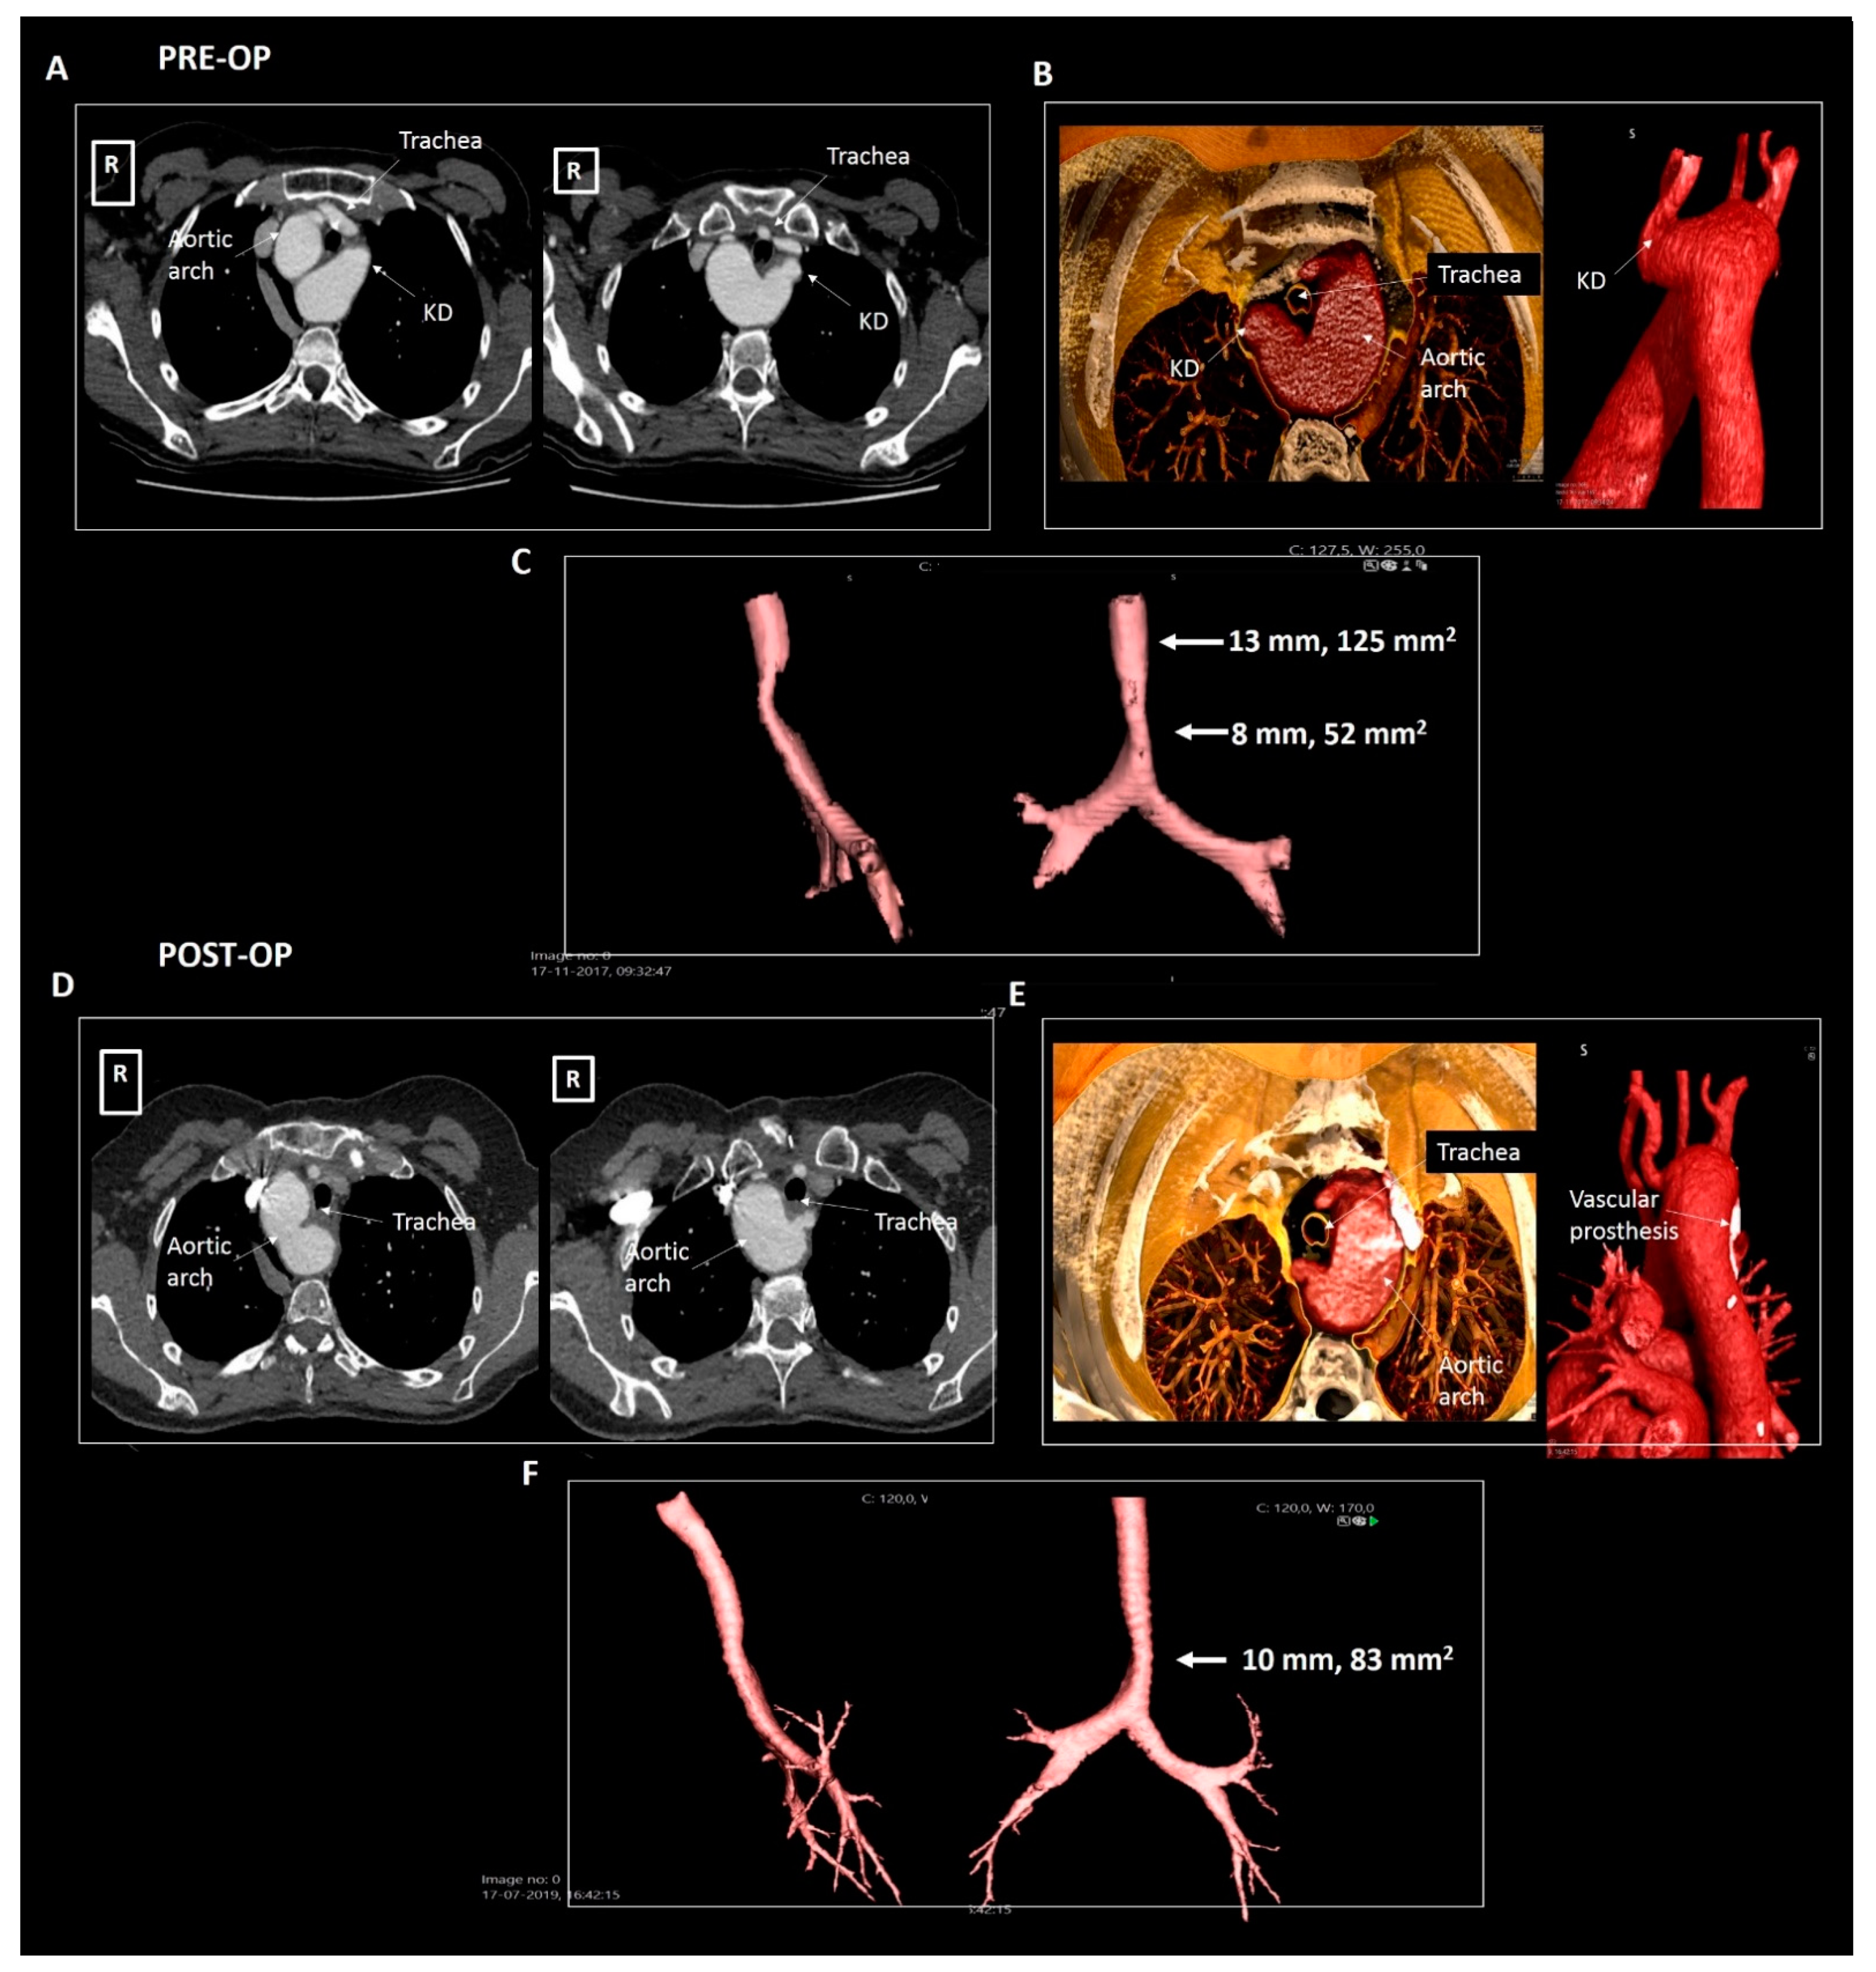

2.3. Patient 3

| Patient 3 | 50 | Female | Right-sided arch, aberrant LSA and KD | Symptomatic tracheal and esophageal compression | 30 × 29 mm, 870 mm2 | Dysphagia and dyspnea | Surgical resection |